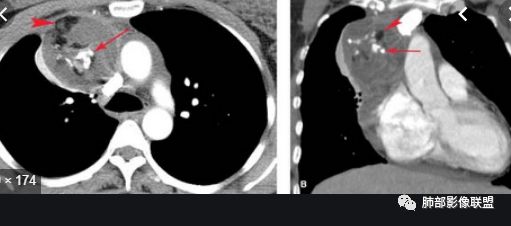

20例畸胎瘤钙化特点

有脂肪密度畸胎瘤

有脂肪,有钙化,钙化为条状,不是块状,偏心

随机翻阅以上20个病例,都是畸胎瘤伴钙化的,发现只有2例钙化是团块状,且都是偏心的。其余18例钙化都是颗粒状、条状和包膜弧形钙化。有9例是多发钙化,且比较散,不聚集。总之,比较少会出现单发中心性的团块钙化。20例均没有,虽然样本少,但是均符合王兆宇老师说的规律。

第一种是弧形钙化,是囊性畸胎瘤的弧形钙化。

第二种条状钙化可能是血管钙化,脉管钙化。

第三种团块状或一颗颗的可能是牙齿,一般都不会太大,而且比较散在。